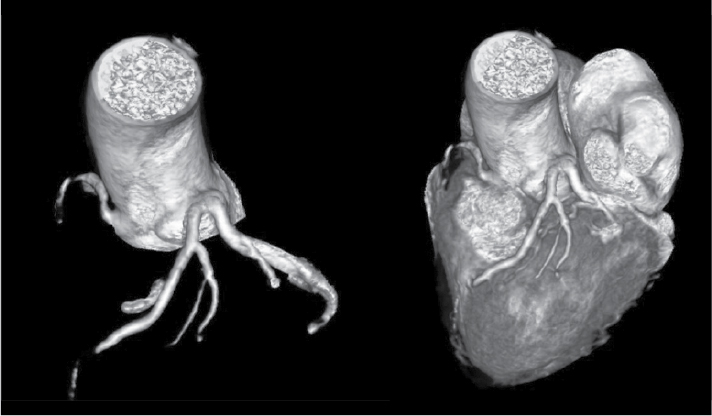

Figure 9. A patient aged 52/F having super-dominant RCA. LCx is absent.

At Nizam’s Institute of Medical Sciences (NIMS), Hyderabad, 770 patients underwent CT-conventional coronary angiography (CAG), on 128-slice single source MDCT (SOMATOM Definition AS ± SEIMENS) during the last 3 years (unpublished data). On analysis, coronary artery anomalies were found in 23 patients (3%). Their ages ranged from 25 to 82 years. Majority of the cases were in 51 to 60 years age group. Among them, 17 were males. The most common anomaly seen was high take-off of coronary arteries, seen in 10 cases. Of them, 2 were having high origin of right coronary artery (RCA) (Fig. 1), 7 were having high origin of left main coronary artery (LMCA) and one was having high origin of both coronary arteries with acute kink at the origin of RCA. Anomalous origin of coronary artery from opposite sinus was seen in 8 cases (Figs. 2-5). RCA from left coronary sinus with interarterial course between aorta and right ventricular outflow tract was seen in 5 cases. Anomalous origin of left coronary artery (LCA) from right coronary sinus with interarterial course between aorta and right ventricular outflow tract was seen in 2 cases. Anomalous origin of left circumflex artery (LCx) from right coronary sinus with retroaortic course was seen in 1 case (Fig. 6). Separate ostia for left anterior descending artery (LAD) and LCx was noted in 3 patients (Figs. 7 and 8). Shepherd crook deformity of proximal segment of RCA was seen in 1 patient. Super-dominant RCA with absent LCx was seen in 1 patient (Fig. 9).

Super-dominant RCA with absent LCx artery is an exceedingly rare congenital anomaly that can be confused with atherosclerotic total occlusion. There are a few such case reports in the literature.8 We observed one such case of super-dominant RCA with absent LCx. Single coronary artery is extremely rare with prevalence of 0.09% (5 out of 5,869 cases) in a study by Fujimoto et al.4 Its clinical implication is complex when the patient develops atherosclerosis in the proximal segment and it can be a challenging situation for either angioplasty or coronary artery bypass grafting (CABG).